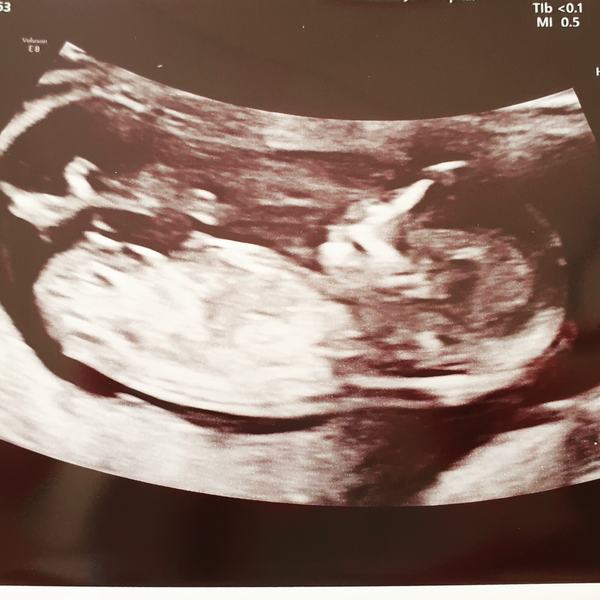

Scan went well today. NT is 1.9 and baby measuring at 13+1. Feeling relieved but can't help but think about all the things that could still go wrong. Trying to be positive though.

Fantastic news @HungryPanda92!! What a great pic too.

@HungryPanda92 - gorgeous pic. So chuffed for you.